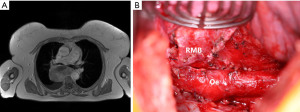

Briefly, she was a 70-year-old female, who has been suffering from increasing dyspnea for the last 6 months. Axial chest CT imaging showed a 90 mm subcarinal mass with compression of the tracheal carina and oesophagus. An EBUS-TBNA was performed. Cytopathological examination was compatible with a leiomyosarcoma. OGD showed extrinsic oesophageal compression without mucosal infiltration. Staging including FDG PET/CT could exclude distant metastases and a gynaecological evaluation could exclude an extramediastinal primary. Preoperative MRI is shown in Figure 3A.

Upfront surgery was favoured over induction chemotherapy. A right posterolateral thoracotomy in the fifth intercostal space was performed. After opening of the mediastinal pleura, the tumor could be freed from the lung, airways, oesophagus and spine. The tumor was removed (Figure 3B) and radical mediastinal lymph node dissection was performed.

After an eventful hospital stay, she was discharged on postoperative day 6. Histopathological examination confirmed a completely resected conventional G2 leiomyosarcoma. All 37 mediastinal lymph nodes were free of tumor. She underwent adjuvant chemotherapy with 5 cycles of dacarbazine and doxorubicin followed by 60 Gy of radiation. Follow-up at 10 months did not show evidence of recurrence.